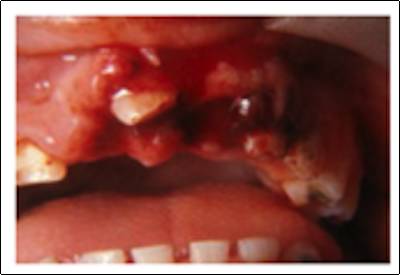

皰疹性口炎是一種病毒(單純皰疹病毒,Herpes Simplex Virus,HSV)引起傳染嘅疾病,主要係見喺細細個嘅細路度。可能係寶寶第一次接觸皰疹病毒,佢會導致高燒、水皰、口腔潰瘍和牙齦炎症。

水皰常見於嘴脣邊緣,不過口腔入面有時都會出現皰疹。佢係有傳染性嘅,水皰中充滿了水樣液體,一旦寶寶發生原發感染,病毒會留喺身體裏,可能會反覆出現。

皰疹性口炎通常在1到2週內會自動痊癒,一啲嚴重嘅病人可以用抗病毒藥物治療。